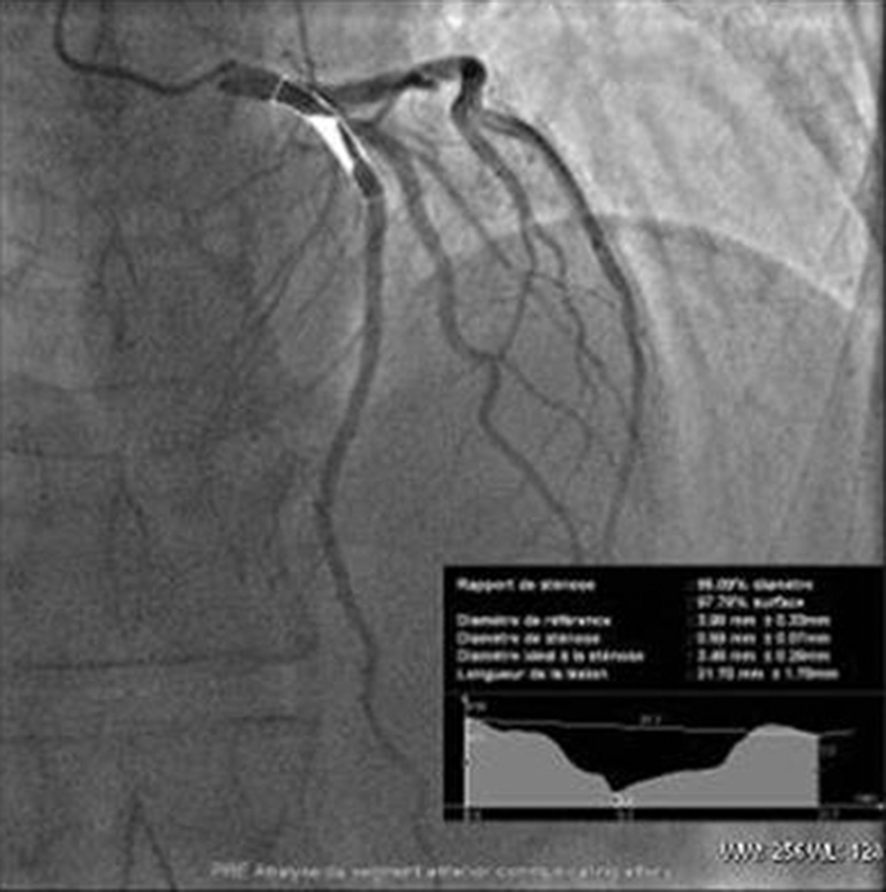

La coronarographie est l’examen clé. Elle montre le nombre, le degré du rétrécissement complet (occlusion) ou partiel de l’artère, sa topographie (figure 40.4), et permet le traitement dans le même temps par angioplastie au ballon, associée le plus souvent à la pose d’un stent.

Fig. 40.4. Coronarographie permettant de montrer et de quantifier le degré de sténose à l’aide d’un logiciel de quantification.

Source : CERF, CNEBMN, 2022